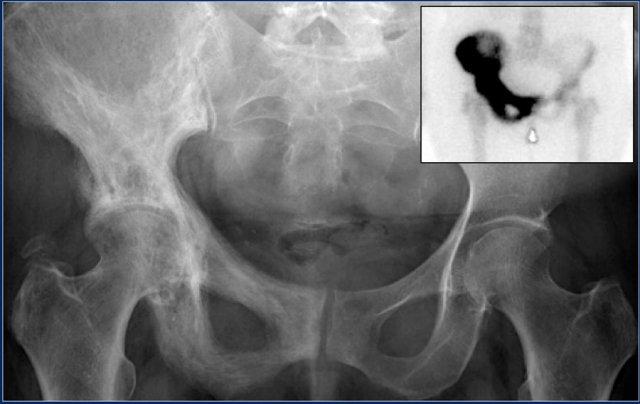

Đây là hình ảnh của một bệnh nhân ung thư tuyến tiền liệt.

Lưu ý các di căn xương chủ yếu là tạo xương (osteoblastic) với số lượng nhiều.

Di căn tạo xương (2)

Đây là hình chụp X-quang vùng chậu với một ổ di căn tạo xương hầu như không nhìn thấy ở xương chậu trái (mũi tên xanh lam).

Lưu ý rằng CT mô tả các tổn thương này rõ hơn nhiều (mũi tên đỏ).

Đây là hình ảnh CT của một bệnh nhân ung thư tuyến tiền liệt.

Lưu ý các di căn tạo xương không rõ ranh giới lan rộng.